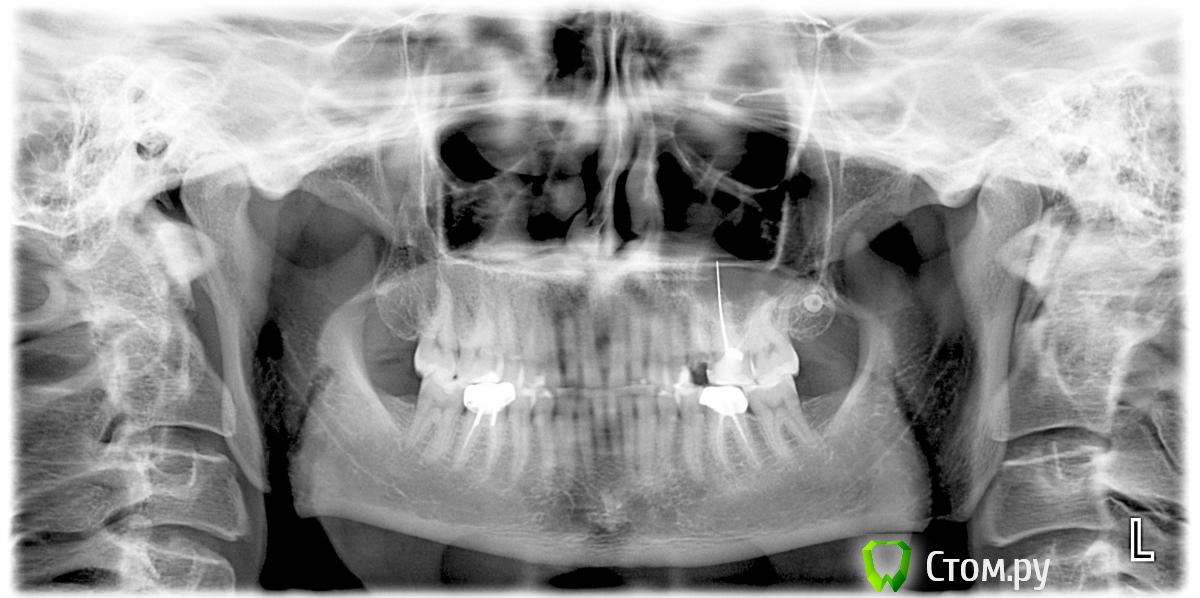

Excellent Опубликовано 11 марта, 2014 Автор Поделиться Опубликовано 11 марта, 2014 Вот снимок. общался сегодня еще с одним стоматологом, первый из 8 стоматологов, который предложил вместо импланта сделать мост. Для этого использовать 6ку, которая мертвая (мертвая уже лет 13-14, в ней стоит стержень из какогото сплава с серебром). Ссылка на комментарий

Excellent Опубликовано 12 марта, 2014 Автор Поделиться Опубликовано 12 марта, 2014 Это мне в частной клинике сказали, врач-хирург. скажите, стоит ли рассматривать установку моста, как альтернативу импланту?Как раз один из соседних зубов (6ой) мертвый (в нем стоит штифт, виден на снимке).С точки зрение финансов выходит в 2,5 раза дешевле чем установка имплантов. Ссылка на комментарий

red_butler Опубликовано 13 марта, 2014 Поделиться Опубликовано 13 марта, 2014 Зачем 26з перелечивать? плохо вылечены корневые каналы + штифт выведен. Хорошо бы и кт сделать 1 Ссылка на комментарий